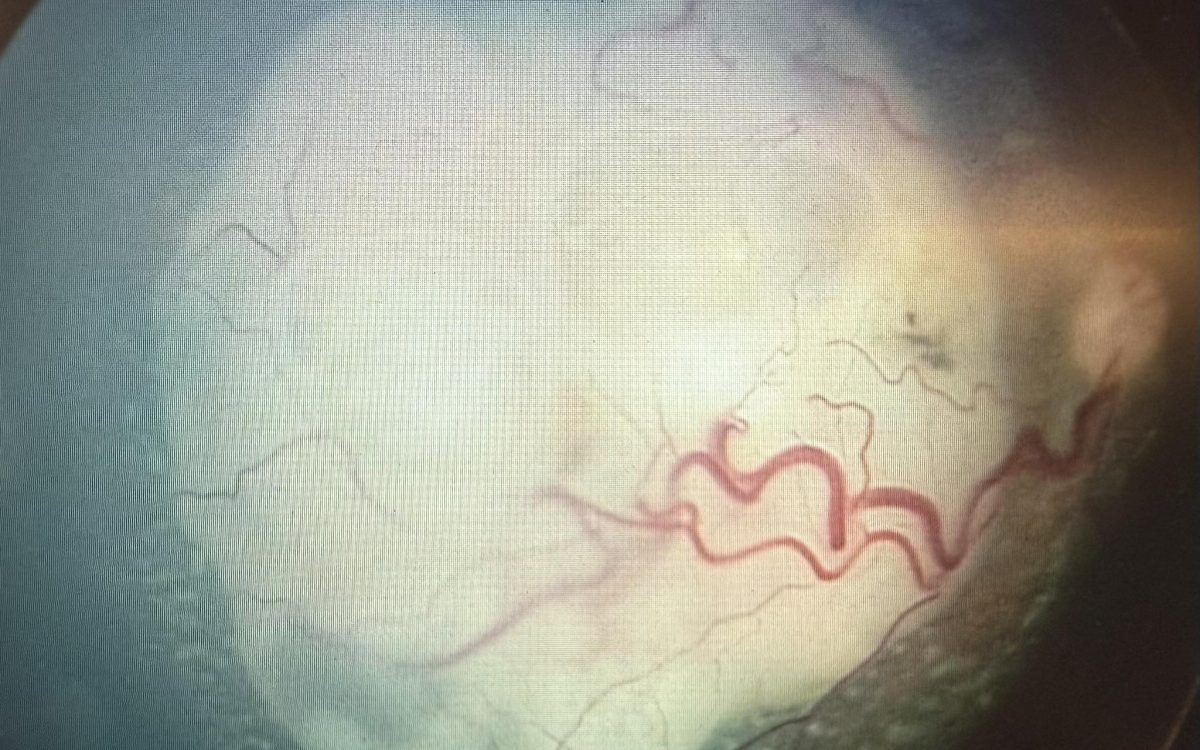

I tumori oculari dell’infanzia, come il retinoblastoma, mettono alla prova la medicina, ma soprattutto mettono alla prova il cuore. Richiedono precisione, competenza, ricerca continua. Ma richiedono anche ascolto, delicatezza e una presenza costante accanto ai genitori e ai bambini.

In questi quarant’anni la scienza ha fatto passi straordinari. Abbiamo imparato a salvare vite, a salvare occhi, a salvare anche la vista .Ma ciò che non è mai cambiato è l’insegnamento che ho ricevuto da voi, piccoli pazienti: la resilienza pura, la capacità di affrontare terapie difficili con una forza che spesso supera quella degli adulti.